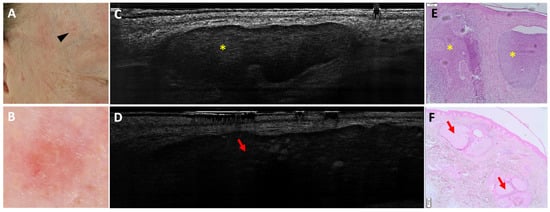

Dermal Mitoses Correlate with Surgical Burden in Lentigo Maligna Melanoma: PRAME for Margin Assessment